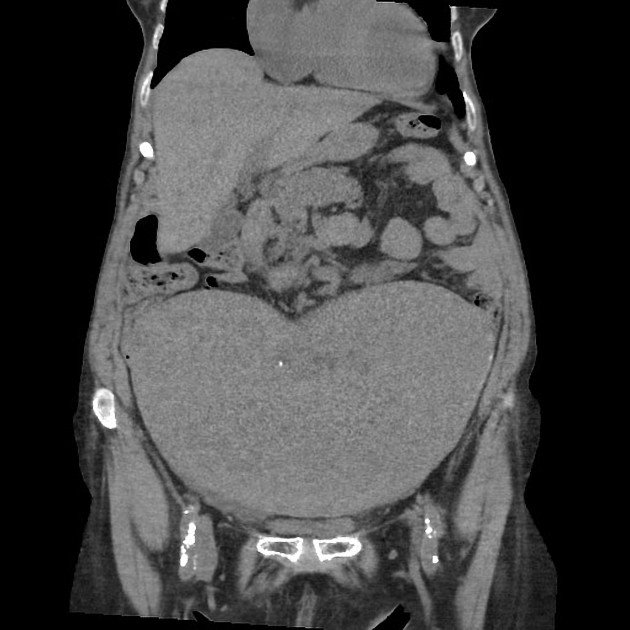

Wandering spleen is a rare medical condition where the spleen is not located in its usual position in the upper left abdomen due to laxity or absence of the ligaments that normally hold it in place. This condition can lead to serious complications, including torsion (twisting) of the spleen’s blood vessels, which may result in splenic infarction (tissue death) and requires emergency treatment.

Wandering spleen occurs when the spleen is mobile and moves to unusual locations in the abdomen or pelvis. This abnormal mobility results from the failure or weakening of the ligaments that normally anchor the spleen. It can be congenital (present at birth) or acquired later in life due to factors like trauma, pregnancy, or connective tissue disorders. A wandering spleen may be asymptomatic or present with pain and a palpable abdominal mass.

• Imaging diagnostics like abdominal ultrasound, CT scan, or MRI to detect spleen displacement